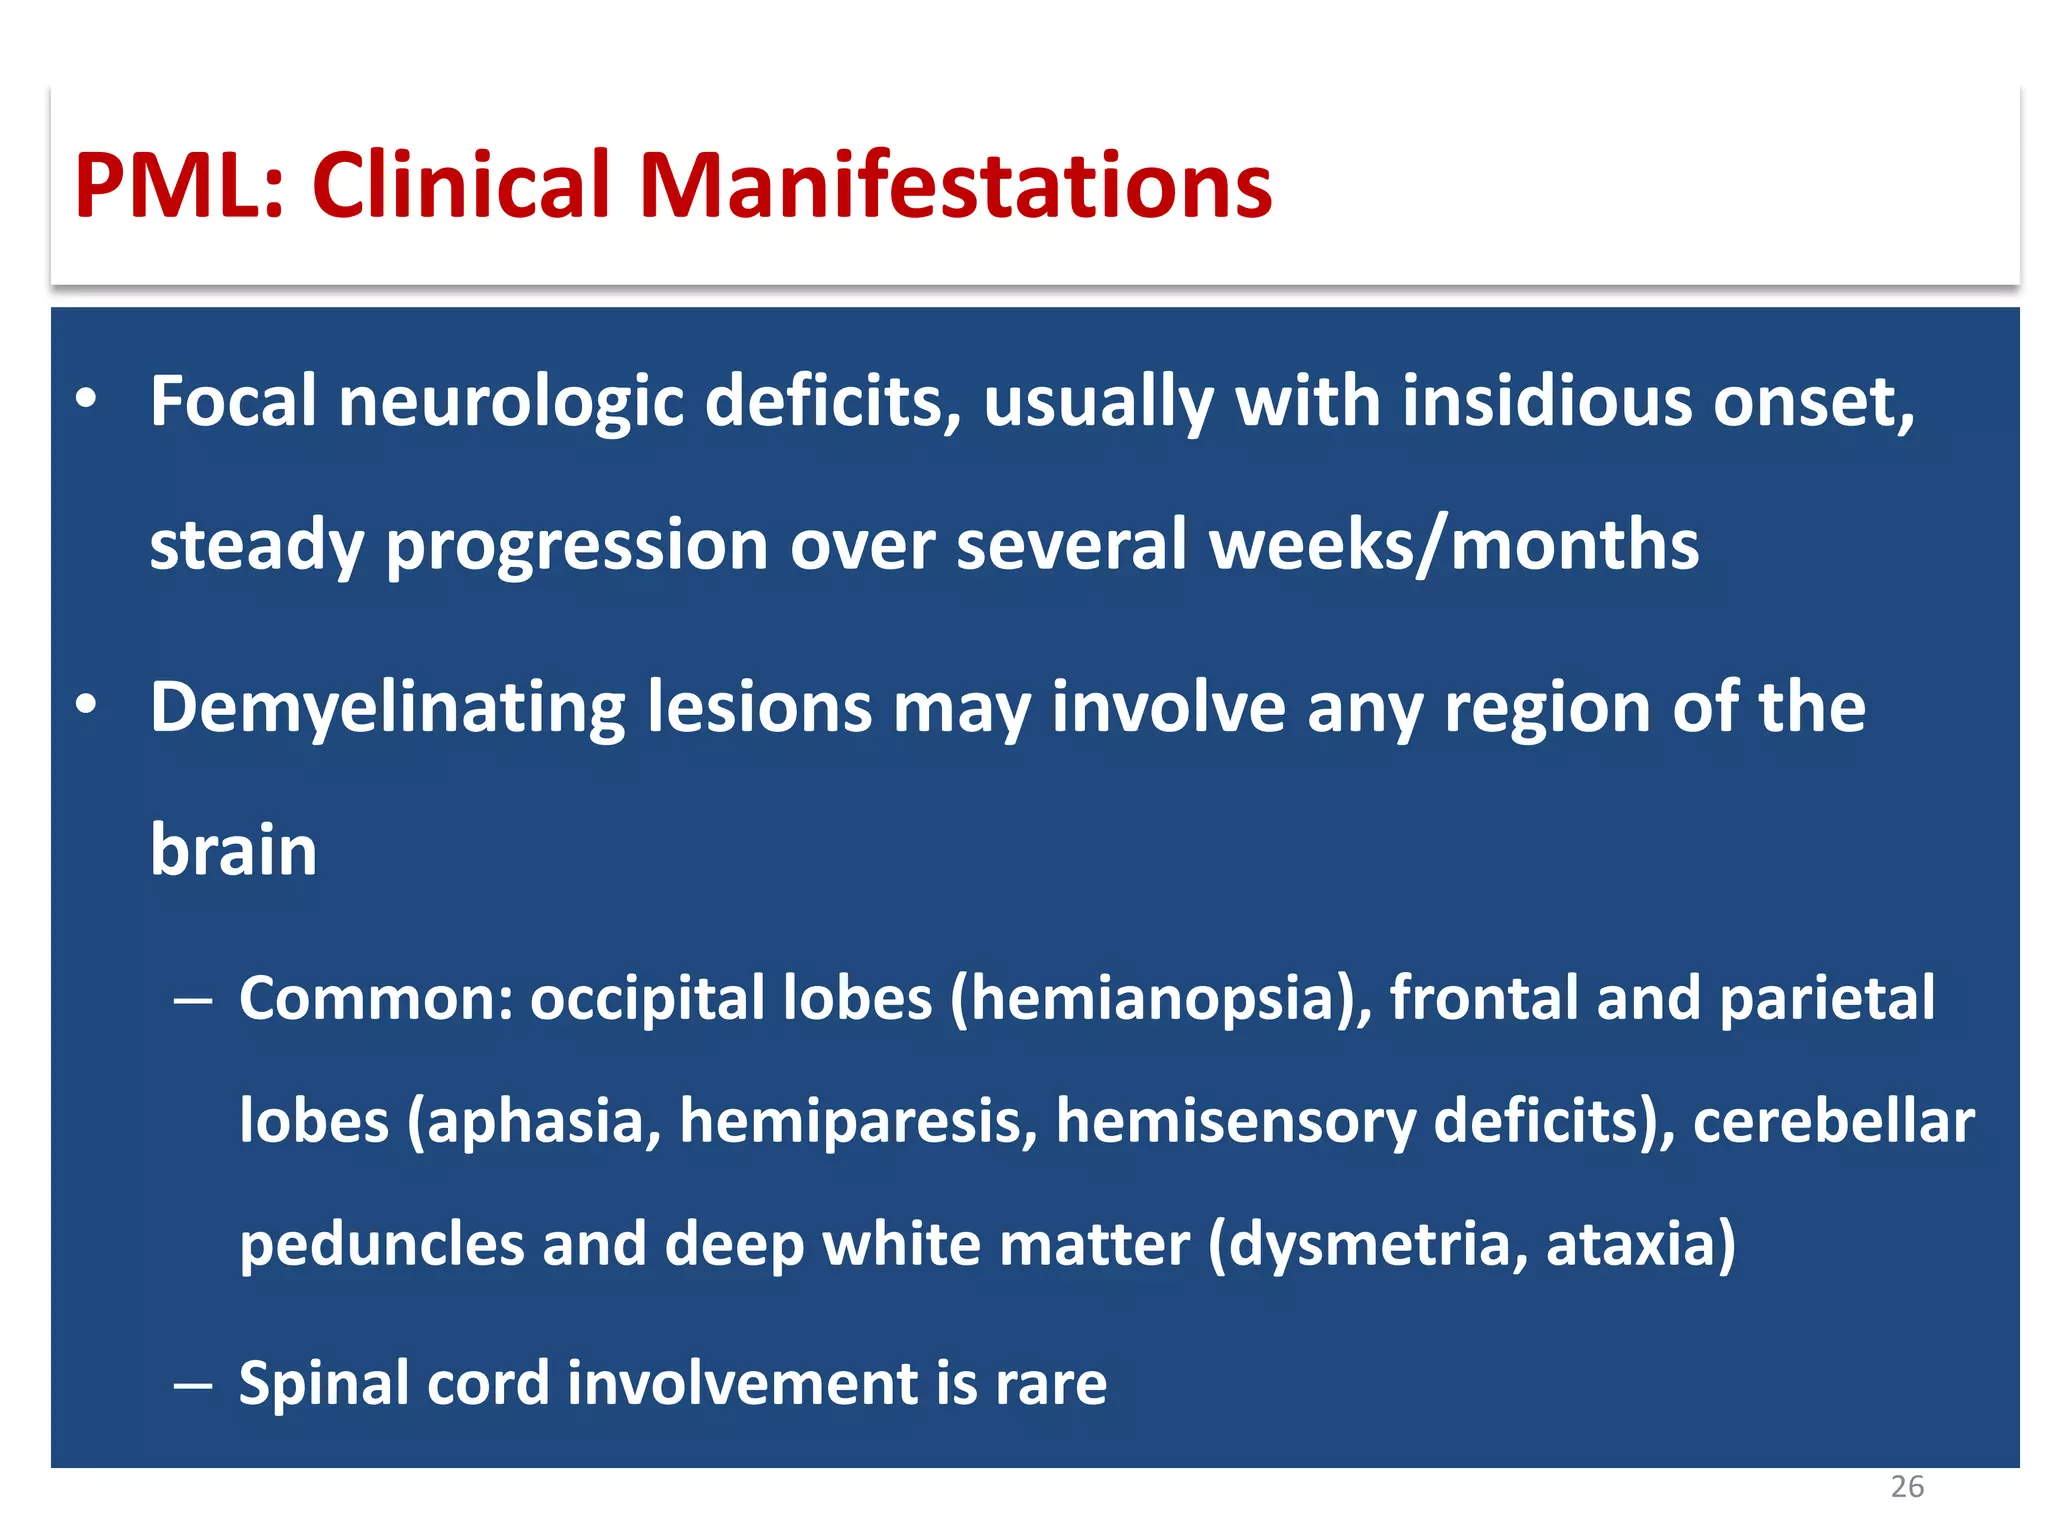

This document discusses progressive multifocal leukoencephalopathy (PML), an opportunistic infection caused by the John Cunningham virus (JCV) that leads to demyelination in the central nervous system. It highlights the epidemiology, clinical manifestations, diagnostic methods, and risk factors associated with PML, particularly in immunocompromised patients and those undergoing immunomodulatory therapies. It also presents data on the incidence of PML in patients treated with natalizumab and other therapies, addressing the relationships between these treatments and the development of PML.